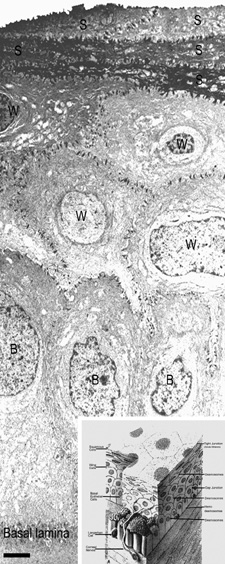

The anterior surface of the human cornea is covered by a transparent, nonkeratinized, stratified (five- to seven-cell layer) squamous epithelium uniformly around 50 μm in thickness that is continuous with the epithelium of the limbus and conjunctiva (Figs. 1, 2, and 3). The basal corneal epithelial cells actively secrete extracellular material (type IV collagen, laminin, heparin, and small amounts of fibronectin and fibrin) that forms an underlying 75-nm thick basement membrane called the basal lamina. On electron microscopy, the morphology of basal lamina appears to be composed of two distinct layers: a 25-nm thick lamina lucida and a 50 nm thick lamina densa (Fig. 3).

Fig. 3. Transmission electron micrograph (3,500×) of the central corneal epithelium with a summary diagram (inset). Microvilli project from the anterior corneal surface into the tear film. S, squamous cells; W, wing cells; B, basal epithelial cells. Bar = 1 μm. (Inset modified from Hogan MJ, et al. Histology of the human eye. Philadelphia, WB Saunders, 1971.)

The cytoplasm of a corneal epithelial cell primarily contains cytoskeletal intermediate filaments and has sparse cytoplasmic organelles (i.e., mitochondria, endoplasmic reticulum, and golgi apparatus). The predominant cytoplasmic filament is keratin, whereas actin and microtubules are two other major types found in corneal epithelial cells. The epithelial cells are held together to one another by numerous anchoring junctions called desmosomes, whereas the basal surface of the epithelium adheres to the basal lamina and underlying Bowman's layer through aa adhesion complex composed of hemidesmosomes, anchoring fibrils (type VII collagen), and anchoring plaques (Fig. 4). The function of the corneal epithelium is twofold: (a) to form a barrier from the environment to the corneal stroma of the cornea, and (b) to form a smooth refractive surface on the cornea through interaction with the tear film.

The epithelial cells differentiate from the basal layer to form two to three cell layers of wing cells and finally to form two to three cell layers of squamous cells (Fig. 3). The squamous cells form a barrier junction because they are surrounded by a continuous encircling band of zonula occludens tight junctions, which serve as a semipermeable, high-resistance (12–16 kΩ cm2) membrane6,7 by closing off the intercellular space. This barrier prevents the movement of fluid from the tears into the stroma and also protects the cornea and intraocular structures from infectious pathogens. The apical surface of the corneal epithelium is specialized to maintain the tear film as microplicae and microvilli on the surface of the most superficial epithelial cells is covered with a glycocalyx and membrane-spanning mucins (MUC 1 and possibly MUC 4); altogether these structures and substances form the 1.0 μm thick mucinous layer of the tear film (Fig. 5).8–10